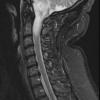

Astrocytoma, IDH-mutant, WHO Grade 2 (3)